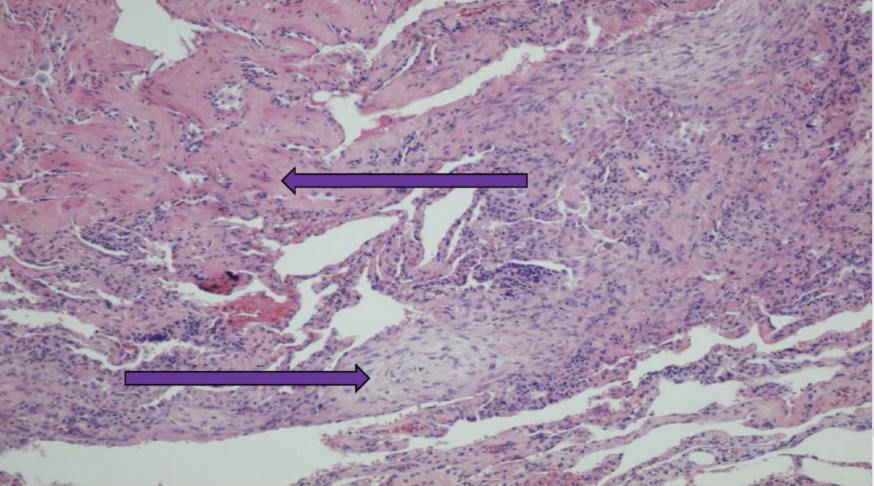

presence of necrosis, lymphocytes, multinucleated giant cells that do not form well defined granulomas. Neutrophils and lymphocytes are invading the walls of the blood vessels. From the lung - Greanulomatosis with polyangitis - Wegner's vasculitis

Granulomatosis with polyangiitis – Wegener’s vasculitis